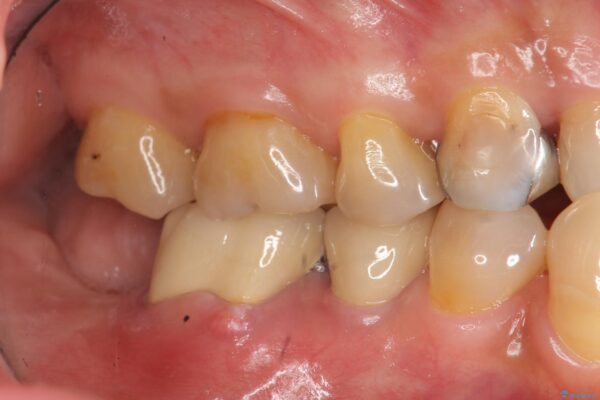

来院主訴

「奥歯で噛むと痛い、いつも膿のにおいがして不快、改善してほしい。」と治療を希望され来院されました。

精査した結果、奥歯の根は破折しており抜歯を避けられない状況でした。

治療前

奥歯から膿のにおいがする インプラントによる機能回復 治療前画像 奥歯から膿のにおいがする インプラントによる機能回復 治療前画像 奥歯から膿のにおいがする インプラントによる機能回復 治療前画像 奥歯から膿のにおいがする インプラントによる機能回復 治療前画像 奥歯から膿のにおいがする インプラントによる機能回復 治療前画像 奥歯から膿のにおいがする インプラントによる機能回復 治療前画像